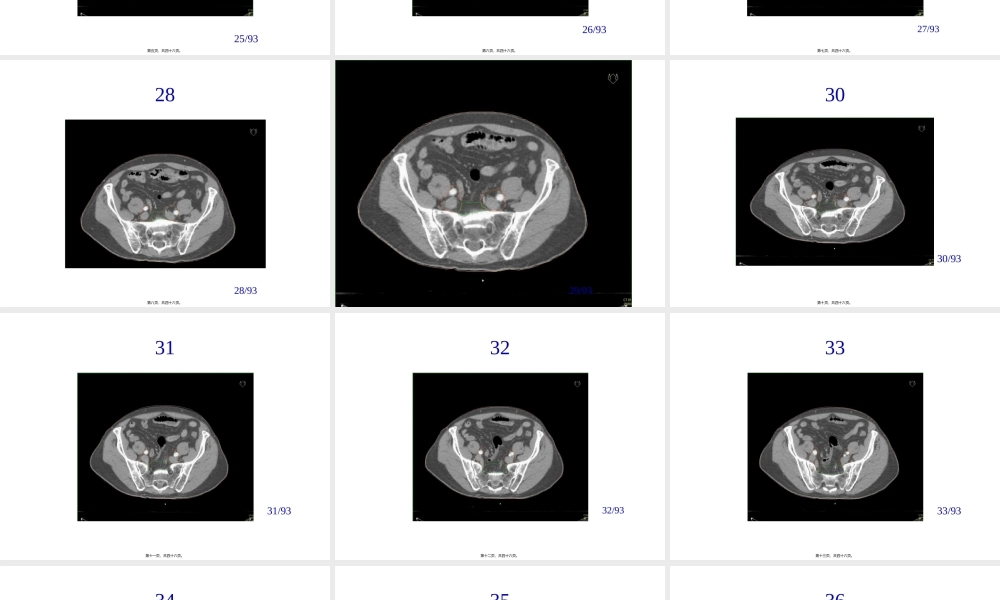

PelvicNodalConsensusCTVContours:HighRisk/LocallyAdvancedAdenocarcinomaoftheProstateColleenAFLawtonMDMedicalCollegeofWisconsin第一页,共四十六页。BasedonDataPresentedConsensusWasObtainedIncluding:•TreatmentofPresacralLNs(subaorticonly)•主动脉弓下骶前淋巴结的治疗•7mmaroundiliacvessels,carvingoutbowel,bladderandbone•髂血管周围7mm,勾画肠道、膀胱、骨骼•CommencecontouringatdistalcommoniliacvesselsatL5/S1interspace•从L5/S1间隙髂总血管远端开始•Stopexternaliliaccontoursattopoffemoralheads(boneylandmarkforIng.ligament)•髂外勾画至股骨头顶端〔Ing.ligament的骨性标志〕•StopcontoursofobturatorLNsattopofsymphsispubis•闭孔淋巴结勾画至耻骨联合第二页,共四十六页。2323/93第三页,共四十六页。2424/93第四页,共四十六页。2525/93第五页,共四十六页。2626/93第六页,共四十六页。2727/93第七页,共四十六页。2828/93第八页,共四十六页。2929/93第九页,共四十六页。3030/93第十页,共四十六页。3131/93第十一页,共四十六页。3232/93第十二页,共四十六页。3333/93第十三页,共四十六页。3434/93第十四页,共四十六页。3535/93第十五页,共四十六页。3636/93第十六页,共四十六页。3737/93第十七页,共四十六页。3838/93第十八页,共四十六页。3939/93第十九页,共四十六页。4040/93第二十页,共四十六页。4141/93第二十一页,共四十六页。4242/93第二十二页,共四十六页。4343/93第二十三页,共四十六页。4444/93第二十四页,共四十六页。4545/93第二十五页,共四十六页。4646/93第二十六页,共四十六页。4747/93第二十七页,共四十六页。4848/93第二十八页,共四十六页。4949/93第二十九页,共四十六页。5050/93第三十页,共四十六页。5151/93第三十一页,共四十六页。5252/93第三十二页,共四十六页。5353/93第三十三页,共四十六页。5454/93第三十四页,共四十六页。5555/93第三十五页,共四十六页。5656/93第三十六页,共四十六页。5757/93第三十七页,共四十六页。5858/93第三十八页,共四十六页。5959/93第三十九页,共四十六页。6060/93第四十页,共四十六页。6161/93第四十一页,共四十六页。6262/93第四十二页,共四十六页。6363/93第四十三页,共四十六页。6464/93第四十四页,共四十六页。65第四十五页,共四十六页。内容总结PelvicNodalConsensusCTVContours:HighRisk/LocallyAdvancedAdenocarcinomaoftheProstateColleenAFLawtonMDMedicalCollegeofWisconsin。TreatmentofPresacralLNs(subaorticonly)。65第四十六页,共四十六页。